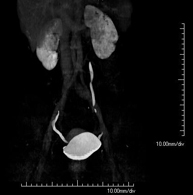

- Virtual colonoscopy

Virtual colonoscopy is a non-invasive technique that allows three-dimensional and two-dimensional visualisation of the large intestine or colon by taking sequential images captured with a state-of-the-art MDCT scanner. The quality of the images allows virtual navigation through the rectum and colon thanks to processing on specialised workstations. Preparation for the test consists of following a low-fibre diet for three days before the test (to cleanse the colon and rectum) and ingesting an iodinated oral contrast agent the day before the test (to mark the stool so that it can be correctly distinguished from any colonic lesions). Unlike fibrocolonoscopy, no sedation or bowel preparation is required. The test is performed in the CT room, where air is blown through a small flexible tube to distend the colon.